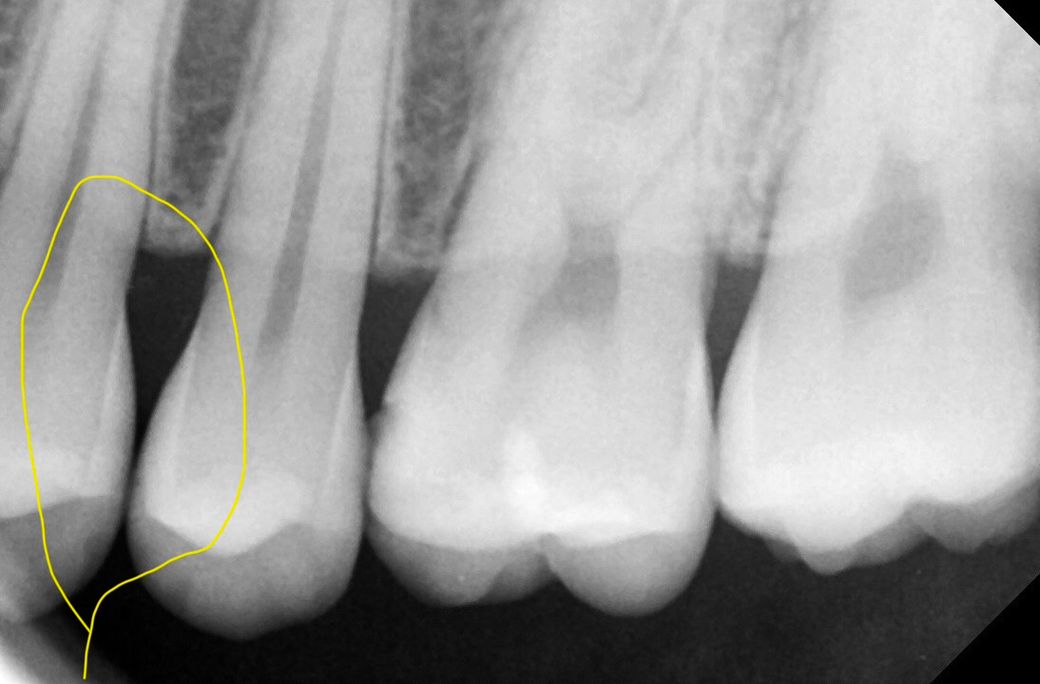

• 4번 째 사진

사진으로는 치아인접면에 색이 변한 부분이 보입니다. 하지만 X레이 사진으로는 충치가 커 보이진 않습니다. 따라서 치실 등으로 해당 부위를 관리해 보는 것이 좋을 것으로 생각되며 주기적으로 치과에서 검진을 받아 충치가 커지고 있지 않은지 확인하는 것이 좋을 것으로 생각됩니다.

두가지 모두 맞지만 엑스레이를 조금 더 신뢰하는 편이기 때문에 조금 더 지켜보다 치료할 것 같습니다.

엑스레이 상으로 치아 사이에 충치가 잇는거 같습니다. 크게 진행된 상태는 아니니 일단 관리를 하시면서 지켜보세요.

3. 방사선 사진은 왼쪽 위 작은 어금니 찍은거고, 육안 사진은 오른쪽 위 작은 어금니입니다.